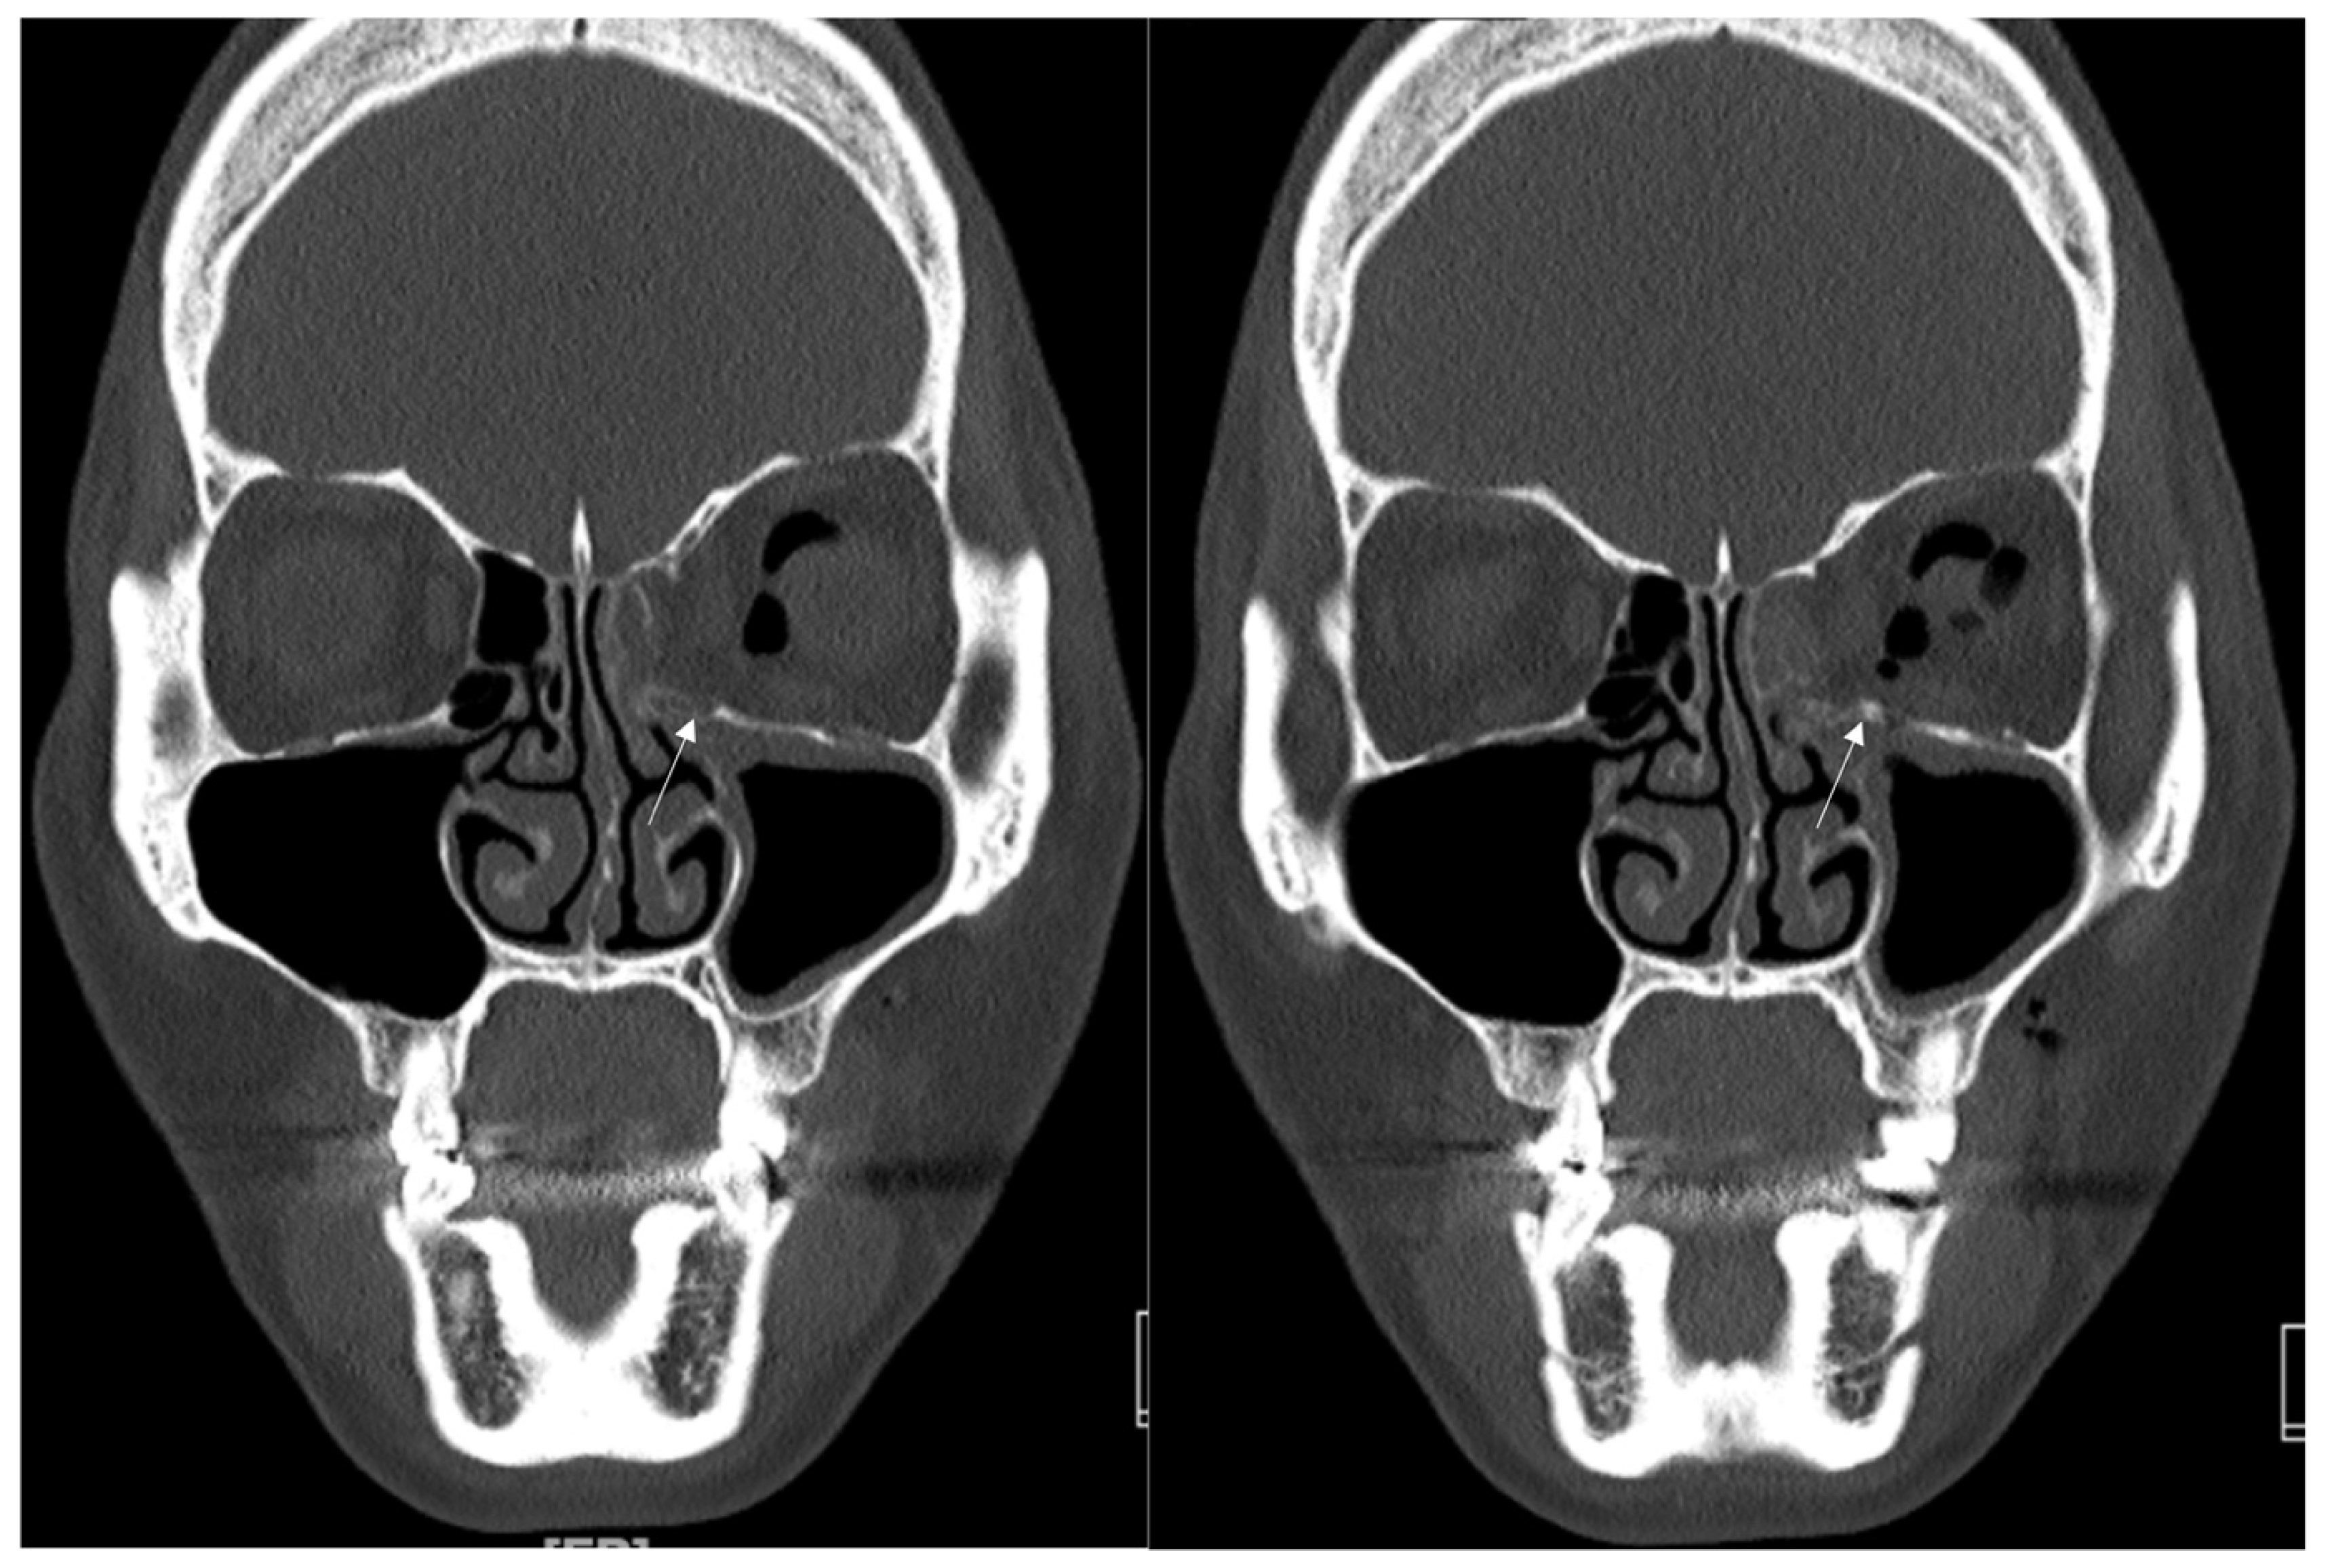

Figure 5. Case 3. Preoperative facial CT scan (coronal and axial view) of the 34-year-old female patient with left medial orbital wall fracture (white arrow). The fracture sites were designated with white arrows.

Figure 6. Case 3. Follow-up facial CT finding (coronal and axial view) of the same patient. The titanium-reinforced porous polyethylene (TR-PPE) plate was placed on the inferomedial orbital wall using a single screw at the inferior orbital rim. (White arrow).

3.3. Case 3

A 34-year-old female patient came to our clinic with left eyeball swelling and ecchymosis caused by a direct trauma to the eyeball. The patient complained of pain and discomfort with eyeball movement (Figure 5). We surgically approached the medial orbital wall fracture two days after the accident. After the subciliary incision, the fracture was exposed. The titanium-reinforced porous polyethylene (TR-PPE) plate was placed on the fracture site using a single screw at the inferior orbital rim (Figure 6). The patient was discharged on postoperative day 2 with significantly improved pain and discomfort.